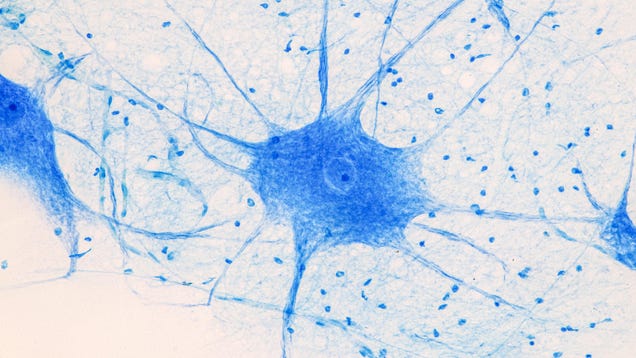

New research links the rare neurological condition Guillain-Barré syndrome to covid-19. The study tracked millions of people in Israel, finding that those with a recent history of covid-19 infection were noticeably more likely to develop Guillain-Barré than those without one. Conversely, covid-19 vaccination appeared…